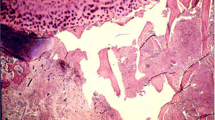

The primary pathophysiologic feature of advanced osteonecrosis is a zone of necrotic bone containing trabeculae with dead osteocytes associated with marrow necrosis and fibrosis [1]. This pathognomonic feature led to the use of the expression “avascular necrosis,” although the international society for the study of the circulation to bone and its disorders, ARCO International (Association Internationale pour la Recherche sur la Circulation Osseuse), recommends using the term “osteonecrosis.” There are several theories regarding the pathogenesis of osteonecrosis [ON], as discussed in several outstanding review articles [2–6]. These can be categorized as (1) extraosseous, (2) intraosseous, or (3) direct cellular. There are many other theories as well, such as intravascular or extravascular pathologies. John Paul Jones, Jr., suggested that multiple etiologies may lead to a final common pathway of intravascular coagulation. He hypothesized that intravascular coagulation is an “intermediary mechanism” in the development of ON [7]. The evidence that intravascular coagulation plays an integral role in the pathogenesis of ON is both direct and indirect and will be the focus of this chapter.

Thrombophilia (increased clots in blood vessels) and hypofibrinolysis (decreased ability to break down clots) have both been implicated as “causative factors” for osteonecrosis [5]. Several investigators have identified thrombi within the arterial and venous circulation of diseased femoral heads (Table 10.1). In their evaluation of human biopsy samples, Ficat and Arlet frequently observed sinusoidal distension, thickening of the arteriolar walls, and arteriolar thrombosis [1]. In three cases of osteonecrosis, Jones observed fibrin thrombi in the subchondral Haversian capillaries, arterioles, and marrow sinusoids [14]. He also noted microfocal marrow hemorrhages with extravasated erythrocytes. Jones suggested that the intravascular thrombosis of the intraosseous arterioles was initiated by lipid embolism and endothelial damage [7, 22]. Saito et al. also observed thrombosed intraosseous arterioles associated with damage to the vascular wall [12]. Starklint and colleagues observed dilated veins and venules within the transitional zone between the necrotic lesion and the “normal” bone [17]. Using the Martius Scarlet Blue stain, tightly packed erythrocytes and fibrin thrombi were detected within these blood vessels, suggesting that the dilated vessels are a consequence of thrombi in other areas. There is, however, considerable debate as to the role of thrombi in the pathogenesis of ON and whether, if it exists at all, it is a primary or secondary event [23]. The lack of thrombi in some histological sections has been explained away by some as a result of the delay in the timing of histological sampling from the onset of disease and that thrombolysis had removed the implicating stimulus [14].